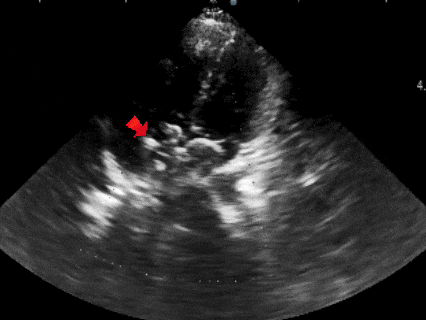

术前复测

多切面测量房间隔缺损直径为

20.5mm×22.0mm×21.6mm

多普勒下可见房水平左向右分流